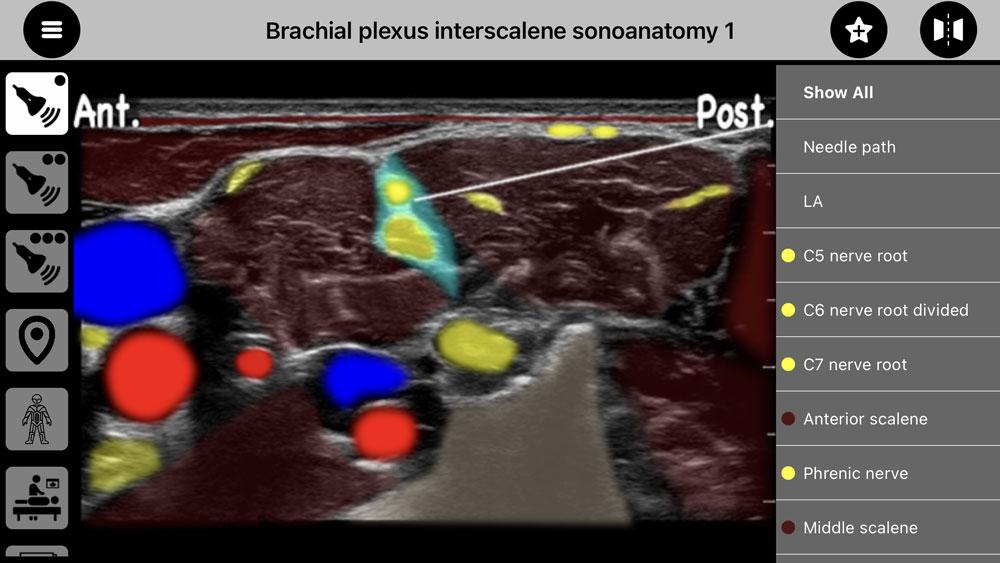

AnSo 是一种方便的资源,旨在帮助麻醉师在繁忙的手术室内以高效的方式识别常见的声解剖学。它是由对超声和局部麻醉教学感兴趣的执业麻醉师创建的。

AnSo 不仅有助于识别目标结构,还有助于识别所有周围的声解剖学。对声解剖学更全面的了解有助于检测解剖变异性,提高手术的安全性和有效性,并促进学习和教学。

- 超过 250 个超声图像,具有超过 1500 个声解剖学颜色叠加,

AnSo 是一种方便的资源,旨在帮助麻醉师在繁忙的手术室内以高效的方式识别常见的声解剖学。它是由对超声和局部麻醉教学感兴趣的执业麻醉师创建的。

AnSo 不仅有助于识别目标结构,还有助于识别所有周围的声解剖学。对声解剖学更全面的了解有助于检测解剖变异性,提高手术的安全性和有效性,并促进学习和教学。

- 超过 250 个超声图像,具有超过 1500 个声解剖学颜色叠加,